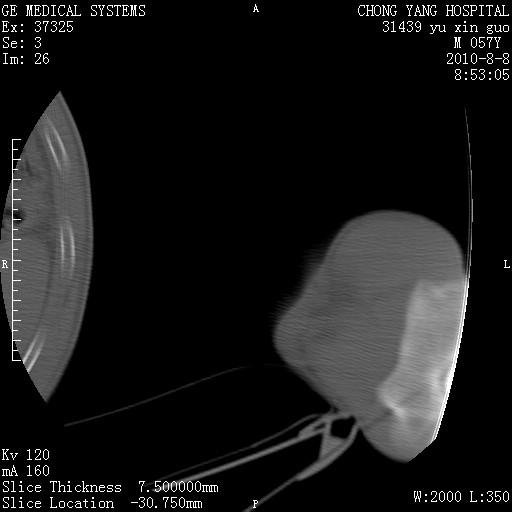

标题: CT28267:M57Y 上臂包块8年余。 [打印本页]

标题: CT28267:M57Y 上臂包块8年余。

包膜光滑、完整的脂肪密度肿块,支持脂肪瘤。